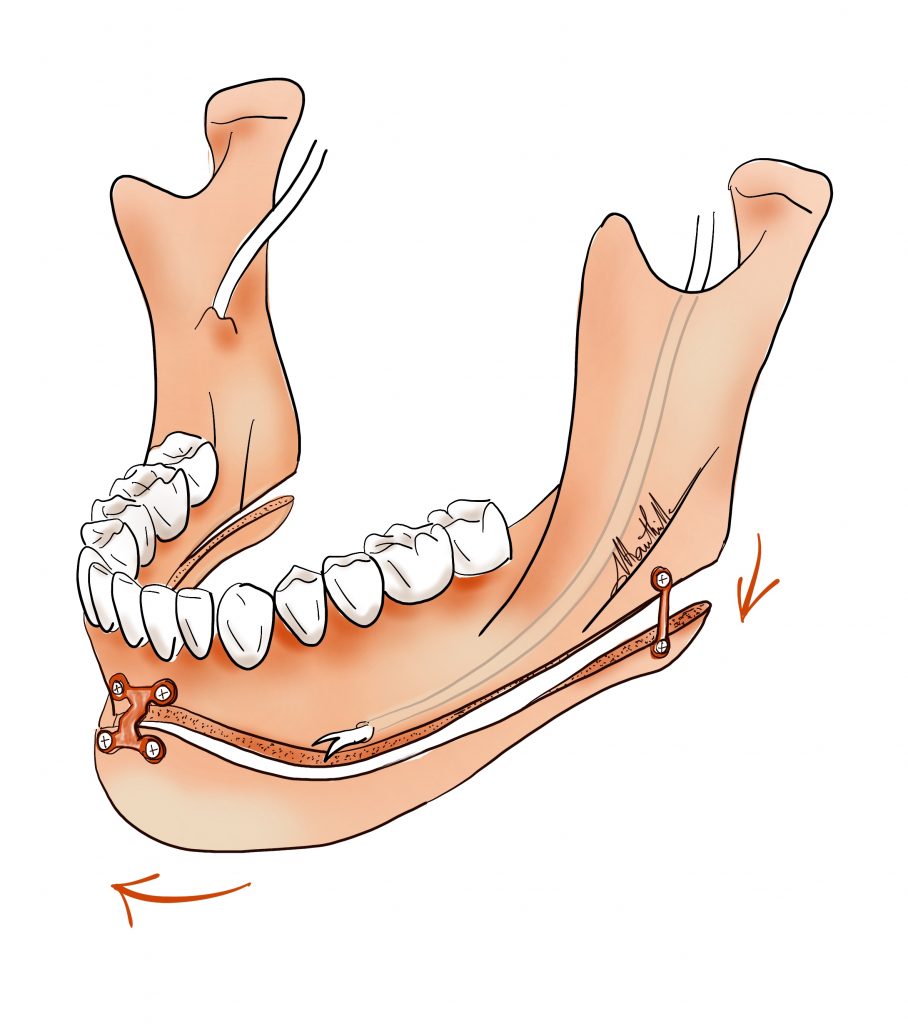

Nous vous présentons un cas de Génioplastie en Chin-Wing, une technique innovante d’ostéotomie du menton qui permet de repositionner à la fois le menton et les angles mandibulaires grâce à un mouvement de “tiroir”. Cette approche, souvent appelée Génioplastie 2.0, permet d’obtenir des résultats spectaculaires.

A la différence d’une simple génioplastie, cette technique chirurgicale plus invasive s’étend jusqu’aux angles mandibulaires.

•Les angles mandibulaires peuvent être abaissés tout en avançant le menton.

•Le mouvement s’effectue dans un plan vertical et horizontal, offrant une amélioration globale du profil du patient.

Cette intervention est particulièrement indiquée pour les patients présentant :

•Un visage dit « hyperdivergent », où la hauteur du visage est augmentée dans sa partie postérieure (arrière de la mâchoire).

•Un menton trop effacé ou situé en arrière, ce qui altère l’harmonie du visage.

Les résultats permettent non seulement d’améliorer l’esthétique du visage, mais aussi d’apporter un équilibre entre les proportions du menton et de la mâchoire.